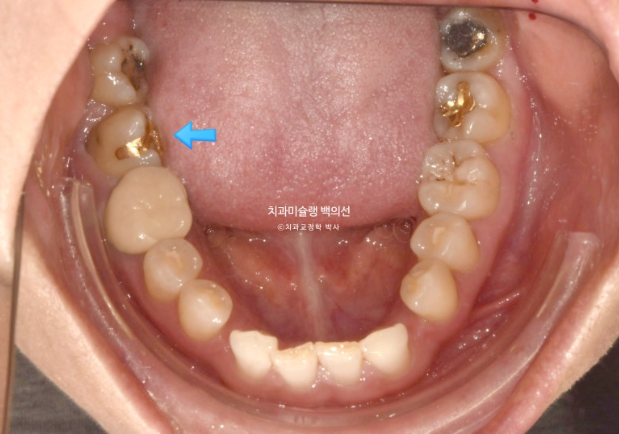

환자분이 모르고 있던 또 다른 문제는 파란화살표 제 2대구치가 혀쪽으로 쓰러져 있는 것 입니다.

24.08

빨간색 치축으로 표시한 치아가 쓰러진 치아입니다.

이 치아는 씹는데 중요한 역할을 하는 치아이므로 반드시 세워주는 것이 좋습니다.

그러려면 쓰러진 큰어금니 바로 뒤 썩은 사랑니는 빼주는 것이 좋습니다